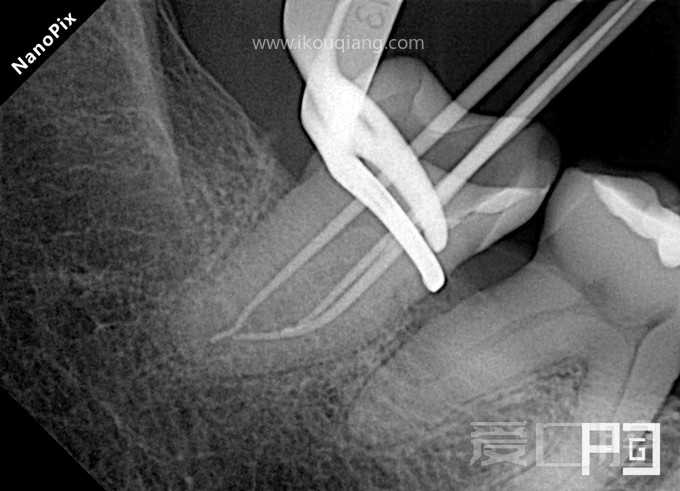

看个根充 —— 下7